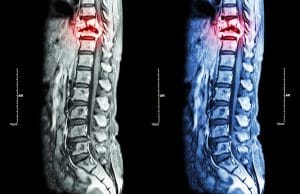

One of the most serious injuries you can sustain is a spinal cord injury (SCI). According to the National Spinal Cord Injury Statistical Center (NSCOSC), car crashes have been the most common cause of spinal cord injuries in the country since 2015.

The spinal cord is at particular risk for damage. According to a 2017 study, rollovers are especially dangerous: “[The] Car rollover mechanism may produce intensive loads on [the] spinal column, particularly [the] cervical spine due to lack of protective devices for this region, and so result in higher risks of neurological injuries.”

The spinal cord is the highway of all the body’s neurological functions. It carries messages from the brain to the rest of the body parts. When the spine is damaged, it often follows that other injuries and complications arise: “The spine can experience trauma during a car crash, and disc herniation can occur, leading to back pain or neuropathy. The pain can be acute or chronic, following a car crash that causes injury to the spine.”